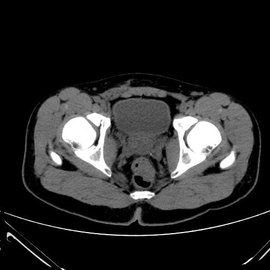

闌尾位於右側髂窩,呈蚯蚓狀,開口於回盲瓣內下方2.5 cm處的盲腸,附著於盲腸的後內側壁。其體表投影在右髂前上棘與臍連線的中外1/3交界處,用手指觸壓麥氏點常有壓痛。

麥氏點又稱闌尾點,位於右髂前上棘與臍連線的中外1/3交界處。急性闌尾炎是外科常見病,在外科急腹症中占首位,所以麥氏點壓痛在急性闌尾炎的診斷中具有重要作用。

1.麥氏點即闌尾根部的體表投影點,麥氏點壓痛是急性闌尾炎臨床上最常見的重要體徵,有助於急性闌尾炎的診斷。